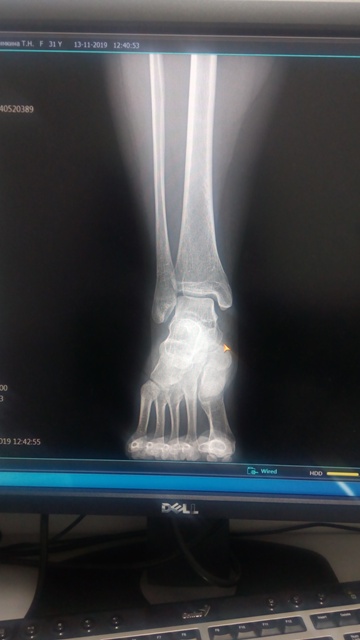

"Цифровой рентген-аппарат JUMONG E (труба Тошиба Е7239Х) работает 4-е года, нагрузка до 70 снимков в день. В основном флюорография и травма.

Одномоментно изменилось изображение при рентгенографии на большом фокусе.

На экране высвечивается: "Error Code 12 ma during exporure tou low".

По нашему мнению процессор генератора обнаружил ток в сети накала меньше допустимого.

При малом фокусе снимки на отлично.

Ваше мнение?"